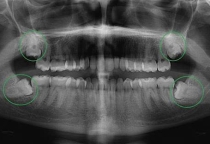

Bước đầu tiên là thăm khám tại nha khoa uy tín để chụp phim, đo khớp cắn và đánh giá độ lệch của răng.

👉 Bác sĩ SV sẽ dựa trên hình ảnh X-quang để lập phác đồ chỉnh nha cá nhân hóa cho từng bệnh nhân.